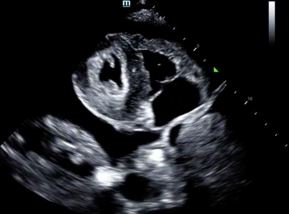

Answer: Pericardial Effusion

- Bedside US shows pericardial effusion with no initial signs of tamponade

- This patient was seen by cardiology and on repeat echo displayed signs of developing tamponade

- She was take for urgent pericardiocentesis where >550mL of fluid was drained from pericaridal sac